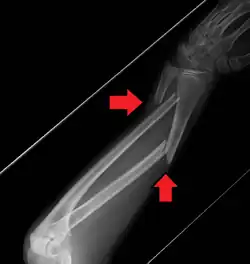

Midshaft fracture of the radius and ulna

A fracture of the forearm can be classified as to whether it involves only the ulna (ulnar fracture), only the radius (radius fracture), or both radioulnar fracture.

For treatment of children with torus fractures of the forearm splinting appears to work better than casting.[7] Genetically determined disorders like hereditary multiple exostoses can lead to hand and forearm deformities. Hereditary multiple exostoses is due growth disturbance of the epiphyses of the radius and ulna, the two bones of the forearm.[8]